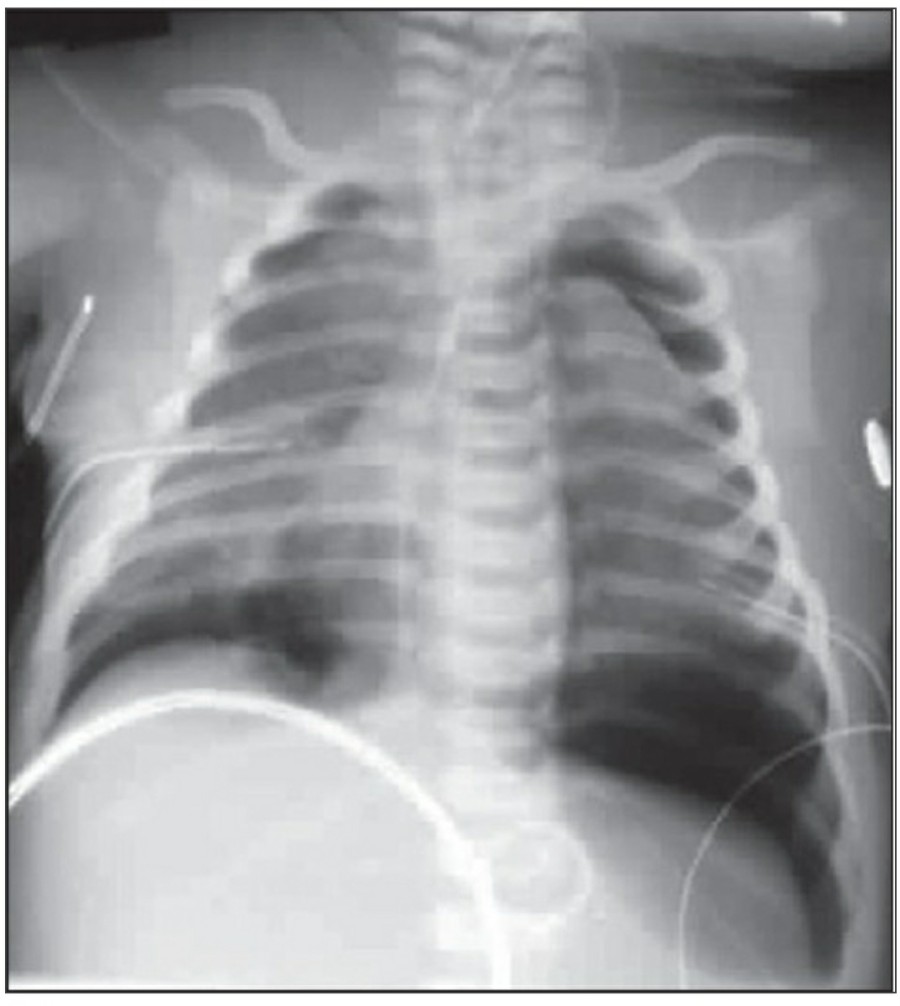

Pleural effusion

방사선 소견상 Pleural effusion은 환자 흉부의 dependent area에 고인다. Erect position에서 확인하기가 쉬운데, 폐의 base에 고임으로써 costophrenic angle blunting을 보이고 lower lobe vessel들의 흐리게 한다. Supine position에서는 확인이 더 어려운데, pleural fluid는 posterior basilar space에 고여서 폐 base 쪽으로 intensity가 증가하는 homogenous density를 보인다. 정상적인 bronchoalveolar marking은 이와 같은 veil-like density 안에서 확인 가능하다. Fluid 양이 늘어나면서 diaphragm의 윤곽이 흐릿해지고 costophrenic angle도 없어지는데, 이 costophrenic angle blunting이 없더라도 pleural space에 1L 정도의 pleural fluid가 있을 수 있다는 것을 기억해야 한다. 그 양이 더욱 늘어날 수록 fluid는 lung의 apex에서 pleural cap으로 나타날 수 있으며, 이는 supine position에서도 확인 가능하다. Pleural fluid는 lung의 medial side에 고일 수도 있으며 이는 mediastinum의 확장으로 보일 수도 있다.

적은 양의 pleural fluid는 꼼꼼히 확인하더라도 supine radiograph에서 놓칠 수 있는데, 만약 chest X ray에서 보이지 않지만 임상적으로 의심이 되는 경우에는 lateral decubitus film으로 확인해 볼 수 있다. Fluid는 dependent position에 고이므로 환자를 의심되는 방향으로 옆으로 눕혀야 한다. Lateral decubitus film은 적은 양의 pleural fluiid는 물론이고 loculated effusion과 free effusion을 확진하는 데도 도움이 된다. 특히 loculated effusion은 한 개 이상의 drain이 필요할 수 있으므로 pleural drainage를 고려할 때 특히 중요한 검사이다. 중환자에서 흔하게 나타나는 subplumonic effusion은 lung base에 존재하는 pleural effusion을 말하는데, chest X ray 상에서 raised hemidiaphragm with flattening and lateral displacement of the dome 형태로 나타나며, lateral decubitus film이 도움이 된다.

Loculated pleural effusion의 진단은 쉽지 않은데, 특히 fissure 안에 있을 때 어렵다. Loculted effusion이 minor fissure 안에 있고 right middle lobe atelectasis가 있다면 supine chest radiograph에서 감별이 어려운데, interlobular effusion은 biconvex edges와 homogenous density로 나타나고 minor fissure는 유지되는 반면, atelectasis는 concave margin과 inhomogenous density로 나타나며 right heart border와 minor fissure가 보이지 않게 된다. 이런 경우 erect lateral radiograph나 CT가 도움이 될 수 있다.